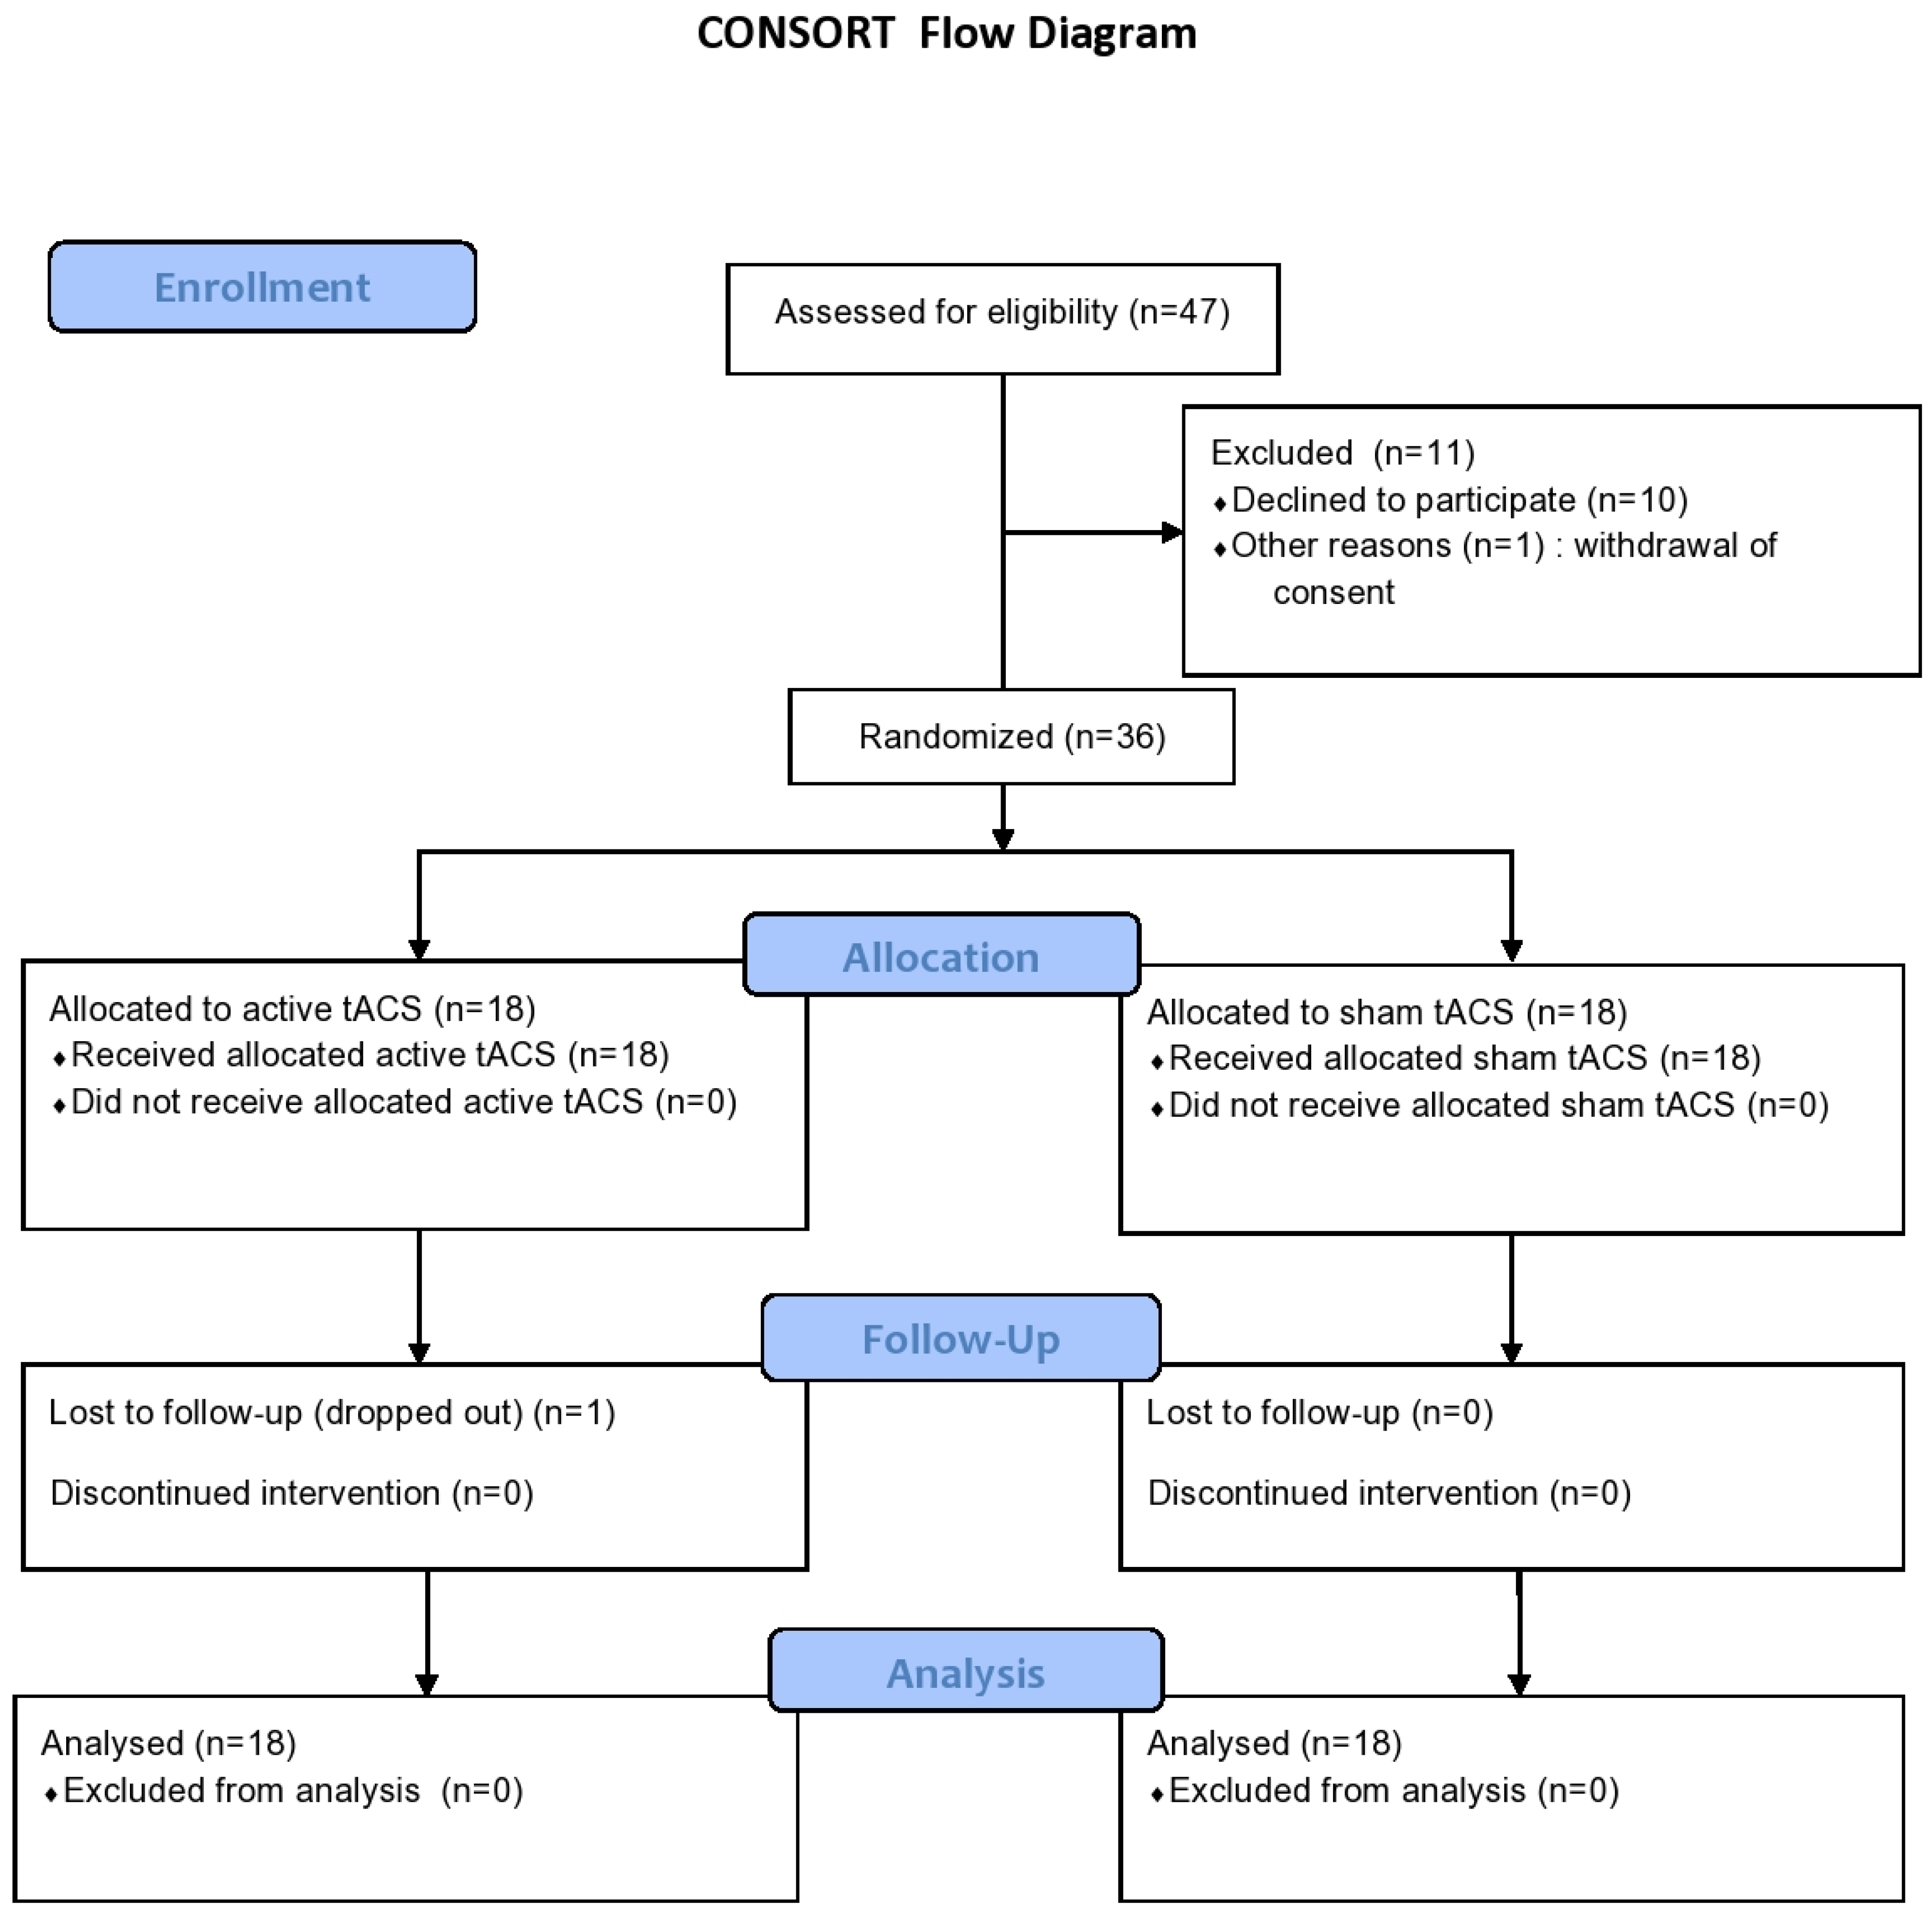

2.1. Participants

2.5. Statistical Analyses

3. Results

3.1. Participant Characteristics

3.2. Primary Outcome